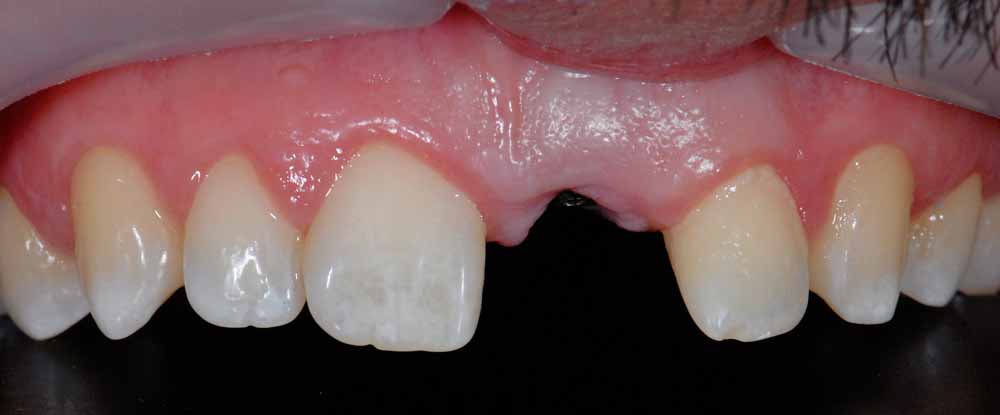

Case Study 1

Missing Tooth

Gap restored with an implant